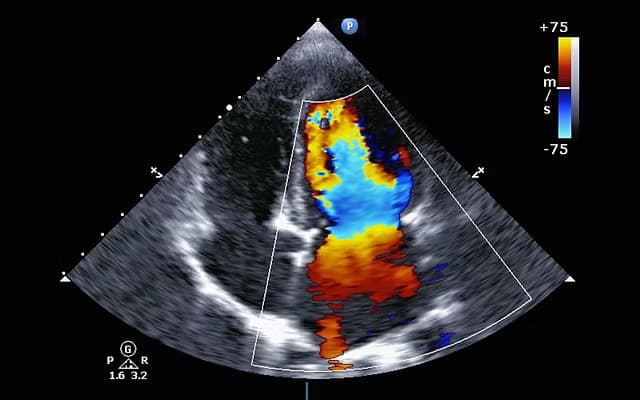

Echocardiograms

Real-time ultrasound imaging to evaluate heart structure and function

Transthoracic Echo

Doppler Imaging